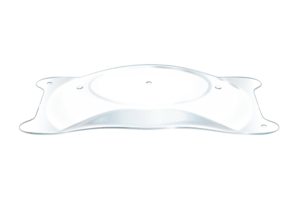

- Collamer is een poly-HEMA-gebaseerd copolymeer met een UV-absorberende chromofoor die UV-bescherming biedt.

STAAR’s exclusieve, premium Collamer®-materiaal

Collamer heeft een bewezen geschiedenis van meer dan 20 jaar met meer dan 3 miljoen ICL-lenzen wereldwijd verspreid. Het is een copolymeer van poly-HEMA en collageen, dat UV-bescherming biedt. Collamer minimaliseert bovendien:

- Ontsteking

- Flare

- Cellulaire reacties8,9